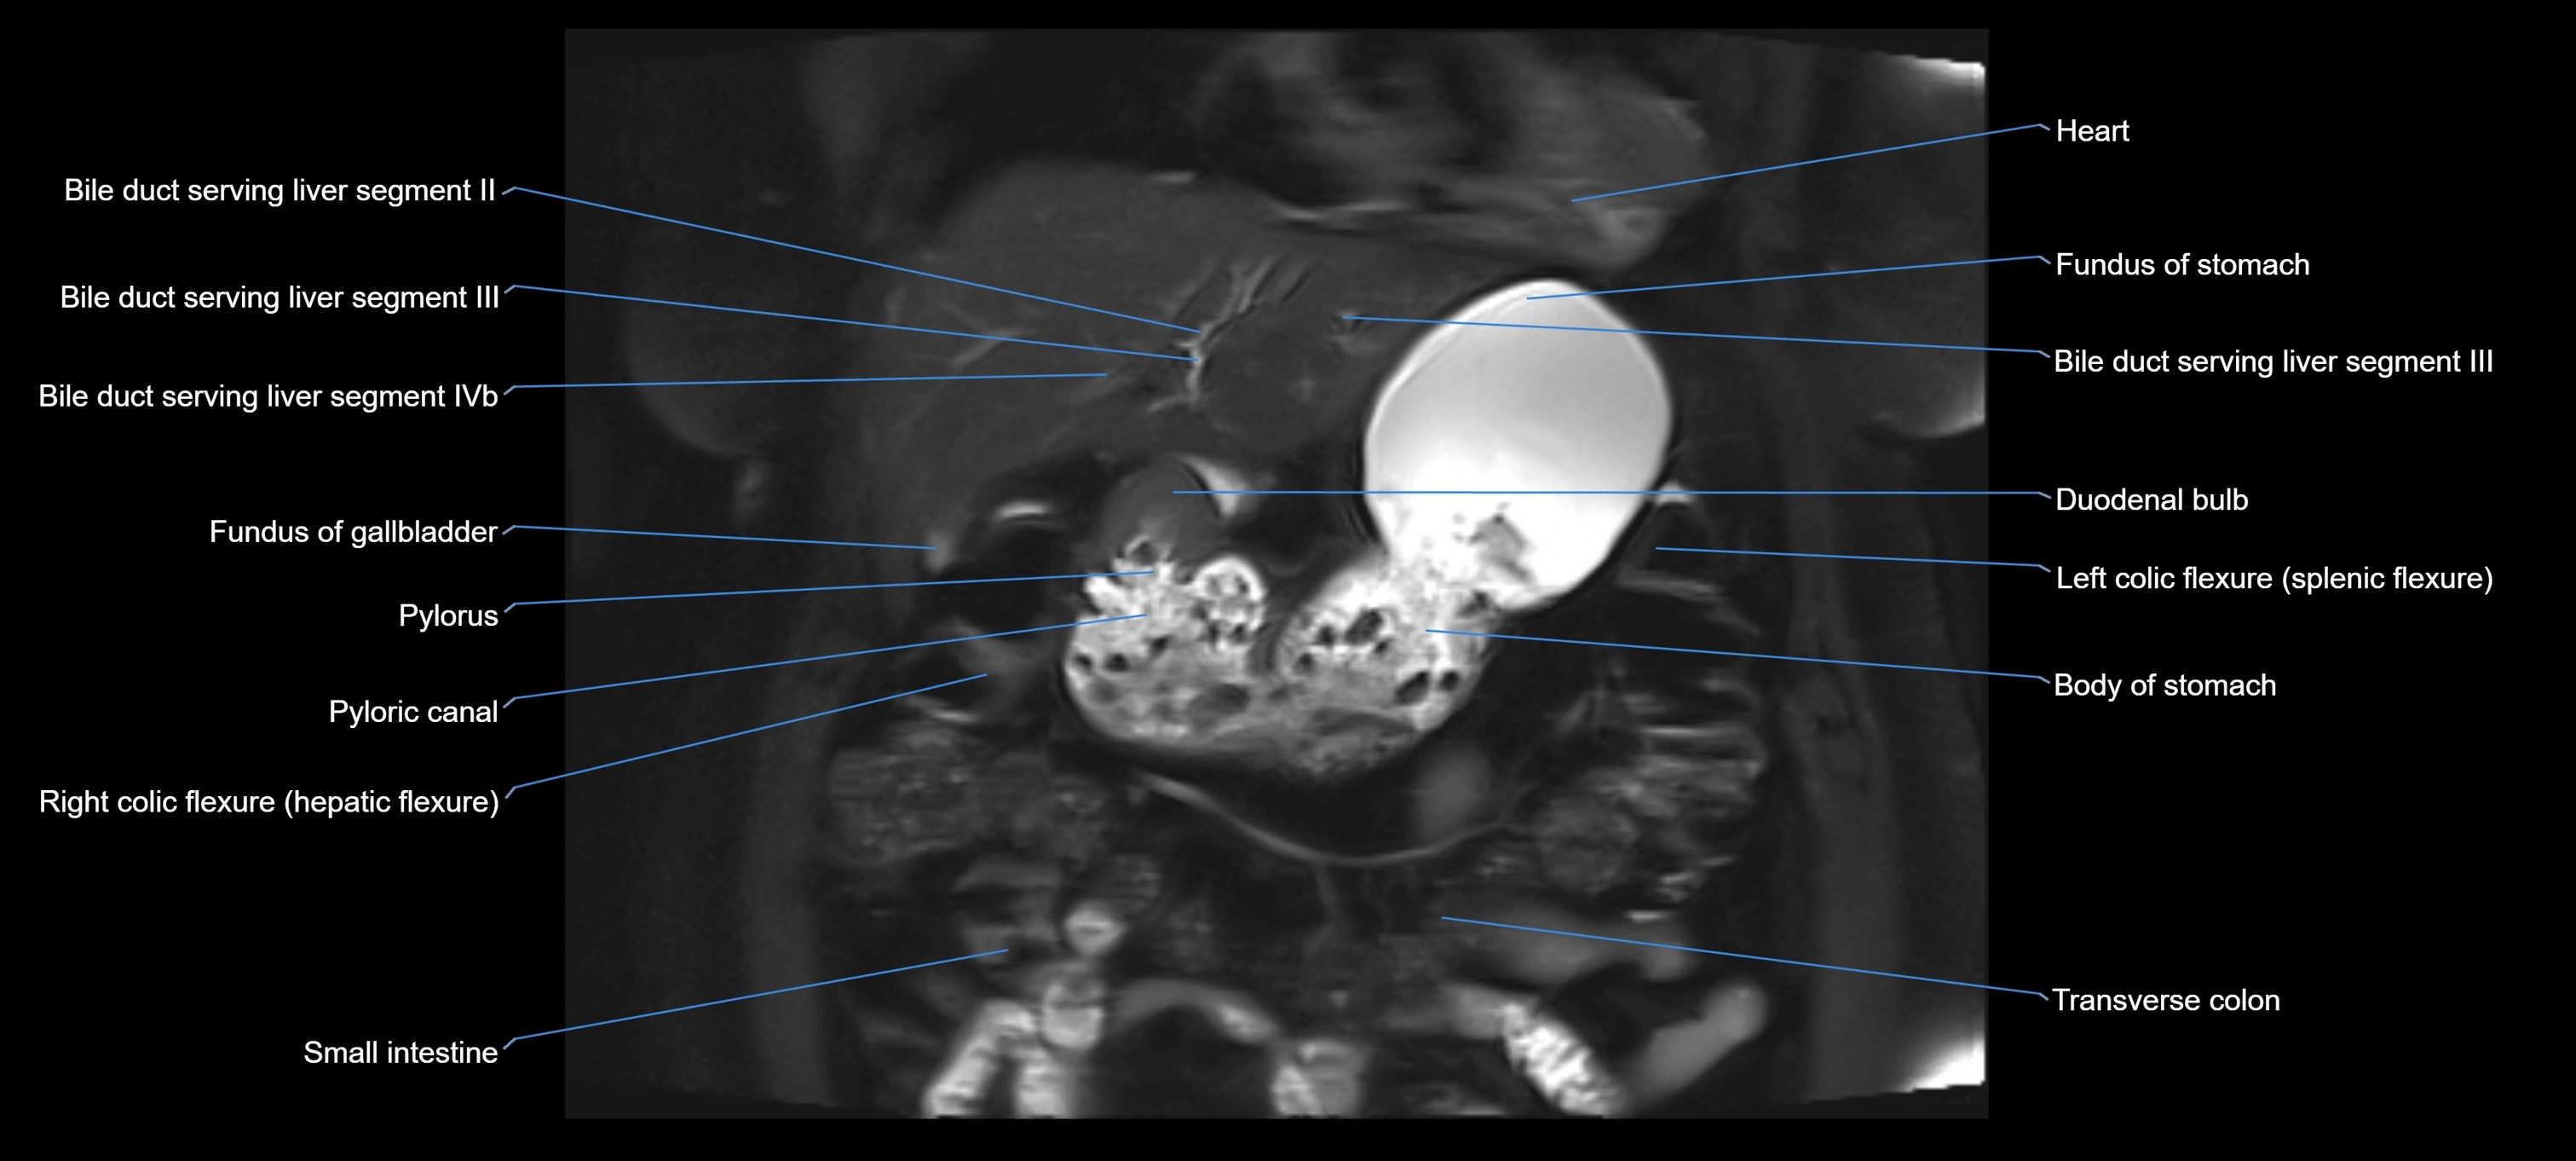

MRI image

image